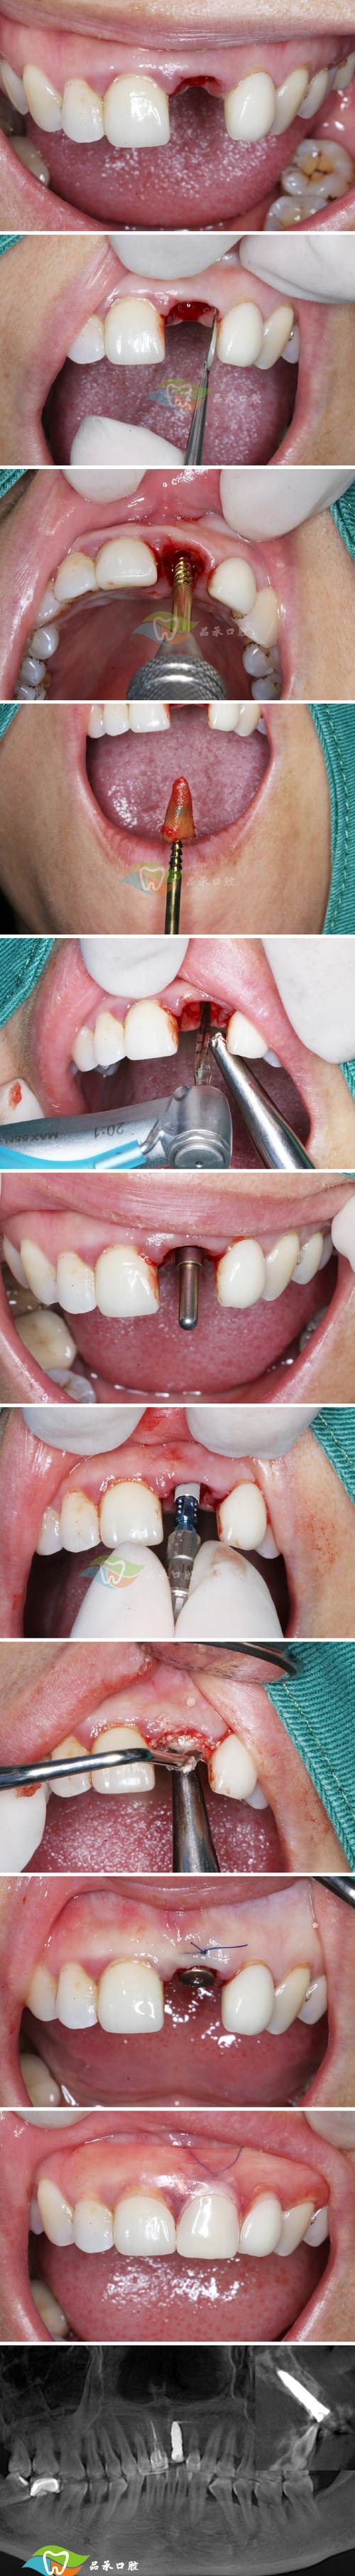

操作流程与技术要点

即拔即种的操作流程严格遵循无菌原则,需由经验丰富的口腔种植医生完成,具体步骤如下(可通过表格清晰呈现):

| 术前评估 | 口腔检查(视诊、叩诊、牙周探诊)、影像学检查(CBCT、曲面断层片)、全身健康评估 | 明确患牙拔除指征,测量牙槽骨骨量(高度≥10mm,宽度≥6mm),判断骨密度,排除禁忌症 |

| 拔牙与窝洞预备 | 拔除患牙,彻底清创拔牙窝,去除炎症组织,修整骨壁 | 尽量保护牙槽骨壁完整性,避免过度搔刮,保留牙槽间隔,为种植体提供初期稳定性 |

| 种植体植入 | 选择合适直径、长度的种植体,植入拔牙窝,确保种植体尖端位于牙槽骨 cortical 下3-5mm | 种植体与骨壁紧密贴合,初期稳定性良好(扭矩≥35N·cm),避免邻牙损伤 |

| GBR(引导骨再生) | 若骨量轻微不足,可植入骨粉、骨膜,促进骨再生 | 严格隔湿,防止骨粉移位,确保生物膜覆盖骨缺损区 |

| 缝合与术后处理 | 无张力缝合拔牙创口,术后拍摄X光片确认种植体位置 | 嘱患者术后24小时内避免刷牙、漱口,服用抗生素预防感染,避免患侧咀嚼 |

术后需定期复查(术后1周、1个月、3个月),观察骨结合情况,一般3-6个月后,若种植体与骨组织结合良好(通过X光片或动度检测确认),可进行二期手术安装基台,再制作并佩戴牙冠,完成最终修复。